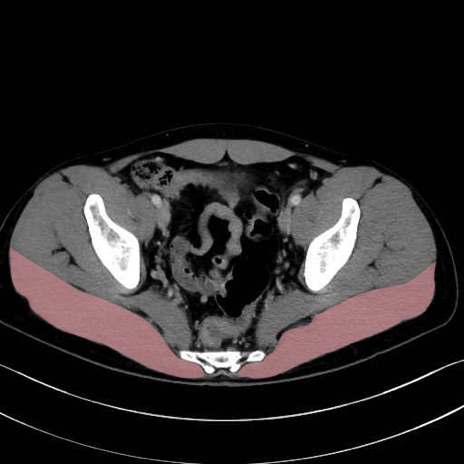

大殿筋 (Gluteus maximus)